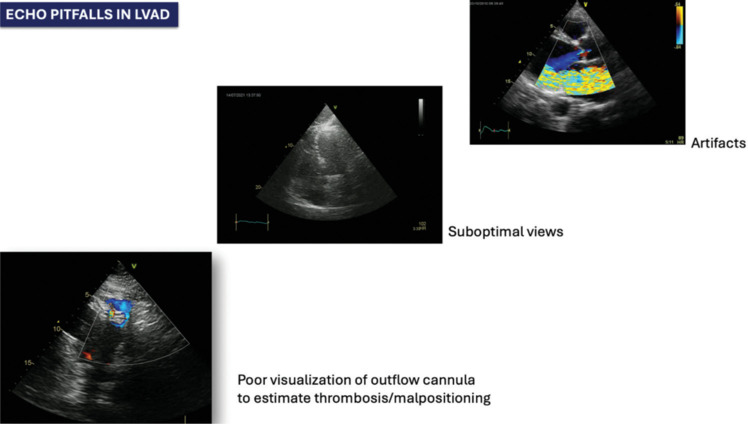

1. lvad已成为晚期心力衰竭的首选治疗手段,然而,植入后仍存在许多潜在的并发症,如右心衰竭、主动脉反流、血栓形成、感染等。在LVAD携带者中,需要进行连续和准确的超声心动图评估,但由于设备的伪影或不良的声窗,有时可能具有挑战性3。左心室卸荷是评估和调整装置功能时需要考虑的主要特征,需要评估许多超声心动图参数4。超声心动图中的斜坡试验可能对优化设备速度和早期识别泵功能障碍具有附加价值。

1. LVADs have emerged as destination therapy for advanced heart failure, however, these are still limited by many potential complications after implant, such as right heart failure, aortic regurgitation, thrombosis, infections 2. A seriate and accurate echocardiographic evaluation is needed in LVAD carriers but may sometimes be challenging, due to artifacts or poor acoustic windows due to the device 3. Left ventricular unloading is the main feature to consider to evaluate and adjust device function and requires many echocardiographic parameters to be assessed 4. Ramp test during echocardiography may be of additional value to optimize device speed and to early identify pump dysfunction.